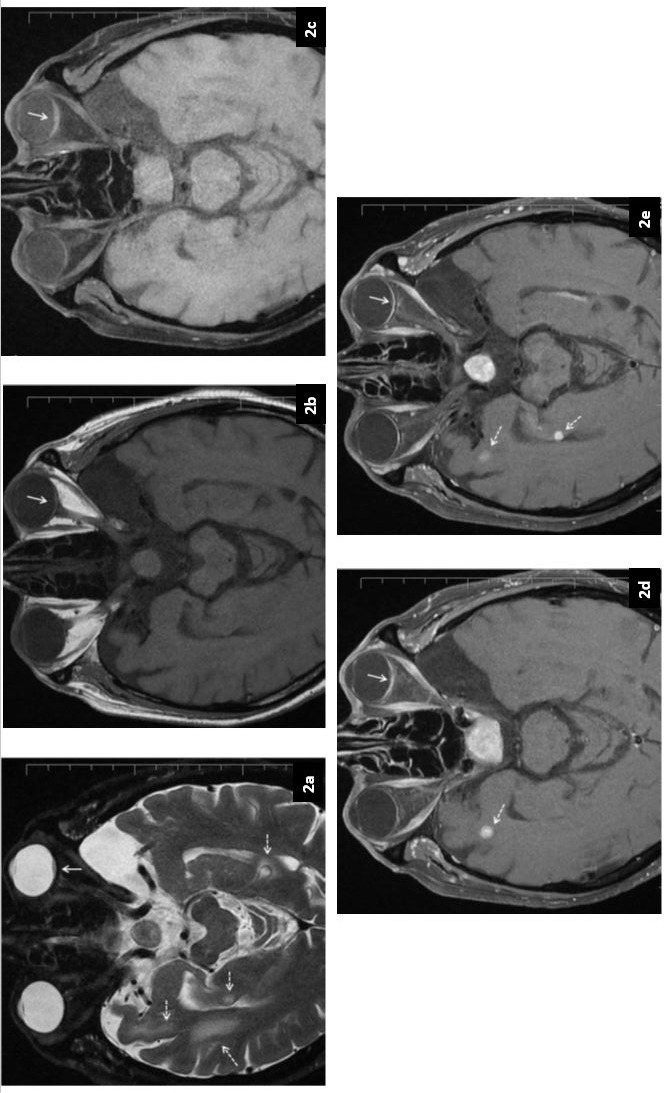

Case report: A 74-year-old male patient had undergone operation due to the diagnosis of rectum cancer two years ago, and lung (L) metastasis developed in the 4th month after the adjuvant therapy, but he refused to receive treatment and remained out of follow-up. The patient presented with complaints of decreased vision and light flashes in his eye 21 months after the diagnosis.

Management and outcome: Ocular examination revealed a choroidal mass and radiologically choroidal and multiple brain metastases were detected. In our case, whole-brain radiotherapy was administered in the treatment since there were also multiple brain metastases. However, as the ECOG (Eastern Cooperative Oncology Group) performance status of the patient was 3-4 after radiotherapy, systemic treatment was not considered appropriate, and the best supportive care was given. The patient died 2 months after the diagnosis of choroidal metastasis.